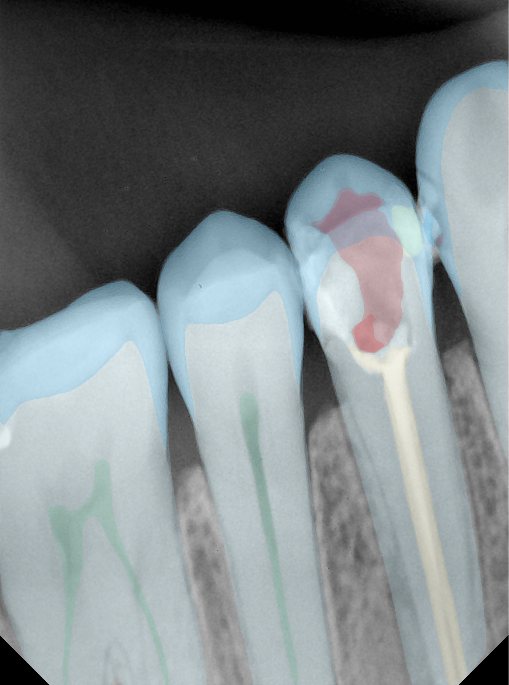

CR/DR 牙齿分割阶段记录

当前进展

- 完成了 CR/DR 牙齿相关分割训练

相关测试

遇到的问题

- 训练过程中出现过 mask 下移问题

- 部分结果会出现 box 填充异常

- mask 边缘仍然有比较明显的锯齿感

参考

第二版算法问题测试

Updated: 2026-04-13(更新日期)

| 第一版 | 第二版 | 是否解决 | |

|---|---|---|---|

![]() | ![]() ![]() 边角识别有问题 龋齿识别不全 牙髓识别不全 | ![]() | 解决 |

![]() | ![]() 边角识别有问题 识别信息有误 自查(牙冠识别不全) | ![]() | 解决 |

![]() | ![]() ![]() 边角识别有误 大范围填充识别遗漏 | ![]() | 解决 |

![]() | ![]() 识别信息不全 | ![]() | 解决 |

![]() | ![]() ![]() 边角问题 牙胶识别不全 牙冠识别不全 | ![]() | 解决 |

![]() 换图片 | ![]() | ![]() 牙冠部分稍微白了一些就识别成小范围修补,部分判断异常 | 部分解决,修复类略敏感,牙冠部分稍微白了一些就识别成小范围修补,部分判断异常。 |

![]() | ![]() ![]() 牙冠识别不全 牙髓不全 根尖炎龋齿识别有误 | ![]() | 解决 |

![]() | ![]() | ![]() | 解决 |

![]() 换图片 | ![]() | ![]() | 解决 |

![]() | ![]() 牙冠识别有误 | ![]() | 解决 |

![]() 换图片 | ![]() ![]() 边角识别有误 | ![]() 修复类敏感 | 部分解决,图像过白,导致修复类判断异常。 |

![]() 换图片 | ![]() 牙冠识别不全 | ![]() 修复类敏感 | 部分解决,图像过白,导致修复类判断异常 |

结论:修复类出现了不鲁棒的情况,后续需要加入轮廓的扩充数据进行增强。